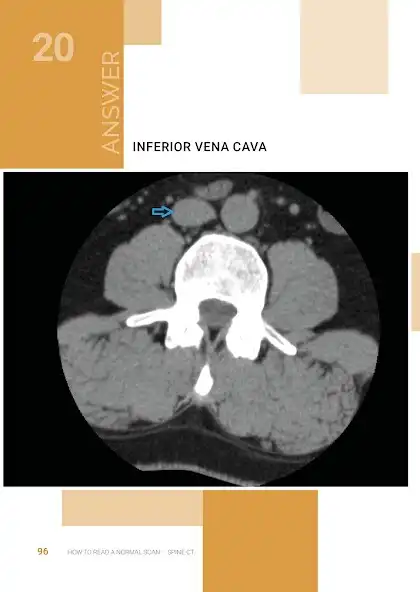

This is an exciting and easy to use Atlas / Quiz of NORMAL Neuroradiology, and attempts to bridge the gap between Anatomy atlases and Radiology atlases. It focuses on the needs of neurology residents and medical students, but anyone who is interested in the radiological anatomy of the brain will find it useful. Using these books as android apps is also reducing production cost , saving printing cost (and trees too in case you like trees). But these same books are also available elsewhere as print versions, but for higher cost.

The objective of the How to Read a Normal Scan series is to familiarize you with NORMAL anatomy as seen on MRI scans and CT scans before memorizing what Hallevorden Spatz or Blah

Blah looks like (sure enough in your Board exam they will want you to identify Blah Blah that no one has seen in 500 doctor years). My hope is, that after reading these books, at the very least you can point out structures on a normal scan and identify exactly what they are. And it is not just about avoiding the embarrassment of ignorance, it is about the sheer satisfaction of knowing what these things are.. If you notice any errors please reach out to me and I will be sure to fix it in the next edition.